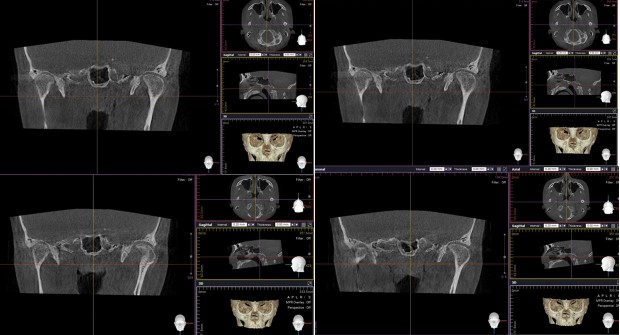

Not long ago, a practicing physician from Prague visited my clinic during orthodontic bracket treatment. She was diagnosed with facial asymmetry and body misalignment, and experienced MCB splint therapy. She was aware that bodily misalignment is related to asymmetry in the facial bones.

There are many around the world—including in Korea—who claim not only to treat TMJ or craniofacial structures, but to treat systemic disorders. Most of them use applied kinesiology for diagnosis and treatment. I myself served for five years as a dental director in a Korean applied kinesiology organization. It is a good discipline. Yet many people—including in Korea—have not gone beyond the level of using applied kinesiology. For example, in the case of the TMJ: applied kinesiology can determine which side of the joint is problematic, and can evaluate how effective a TMJ device is. However, it cannot reveal the direction of asymmetry between the right and left TMJs, or the detailed joint motion. The way to know those is through osteopathic medicine. In Korea, there is almost no practice of osteopathy. 99% of the population do not know the word “osteopath,” and few have experienced osteopathic treatment. It takes a long time to understand the motility of the TMJ.

I have devoted my life to performing orthodontic treatment for people with TMJ problems. Even in the United States, where osteopathy was born and has developed, it seems that almost no one applies the concept of osteopathy when fabricating splints for the TMJ.

Dentistry still remains dominated by the concept of CR (Centric Relation). Many osteopathic physicians have long claimed that the temporal bones move, and treat on that basis, yet the mainstream thinking has not changed. Many dentists still believe that if the mandible (lower jaw) is asymmetric or if the lengths on the right and left differ, surgery is required, and they in fact treat by surgery.